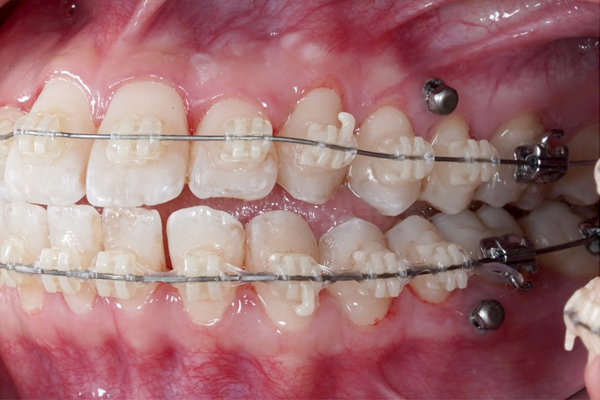

【3ヶ月経過の変化】

• 前歯の重なりが減り、アーチが広がってきました。

• 下の歯はほとんど並びました。

• 見た目も変化してきて患者様も喜んでいます。

【担当者所見】

現在3ヶ月の段階でも、ガタガタがしっかり改善してきています。

これからは噛み合わせを整えて、より美しい仕上がりにしていきます。